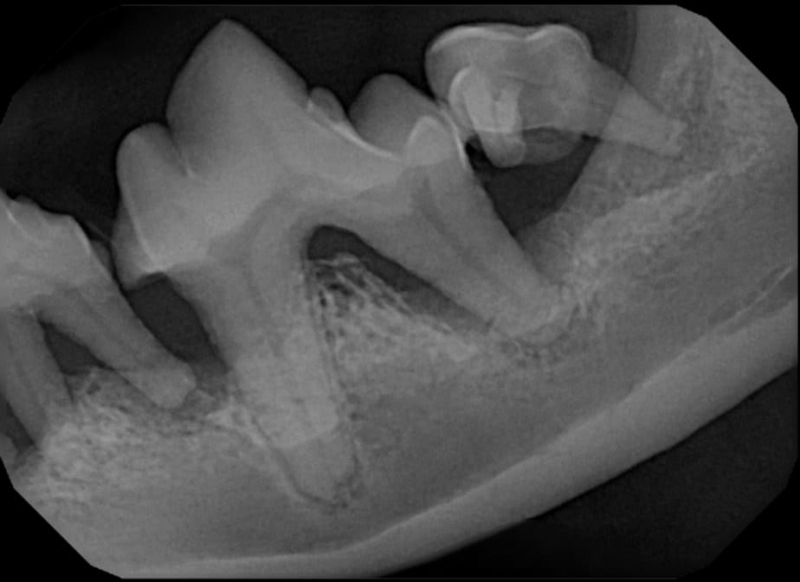

Surgical Extraction of Diseased Teeth

Periodontal disease is extremely common in dogs and cats. Over 80% of dogs and cats over two years of age have some degree of periodontal disease. Periodontal disease is best prevented by yearly professional dental cleanings starting at two years of age and at home brushing at least three times weekly. Brushing should begin at a very early age to allow your new pet to get used to regular brushing. In severe cases of infection or periodontal disease, the teeth may need to be surgically extracted. Extractions should always involve x-rays of the tooth first, as many teeth have multiple roots or may be diseased below where the eye can see. Extracting larger teeth in animals requires oral surgery, equivalent to removing wisdom teeth in people. It is vital that all of the tooth and roots be removed for the periodontal infection to resolve. In cases of important teeth with mild to moderate periodontal disease, multiple periodontal treatments can be offered to help save these teeth.